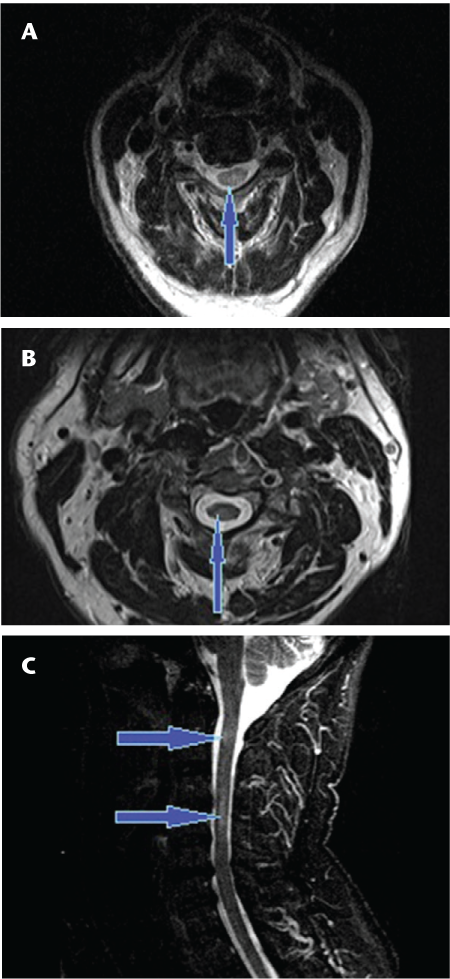

Sagittal T2 fast spin echo images of the cervical (A, B) and thoracic (C) spine showing continuous long-segment linear T2 signal hyperintensity (arrows) involving the spinal cord extending from the cervicomedullary junction to the T8-9 level with predominantly central involvement of the cord in a patient with neuromyelitis optica

Long-segment linear T2-hyperintense lesions in the spinal cord have been shown to be characteristic of NMO myelopathy.16 17 Additionally, in our experience the typical lesions are symmetrical and centrally located in the cord (Figures 1 and 2). Those seen in MS myelopathies are usually less extensive on cross-sectional imaging and are typically asymmetrical and located at or near the periphery of the cord (Figure 3).